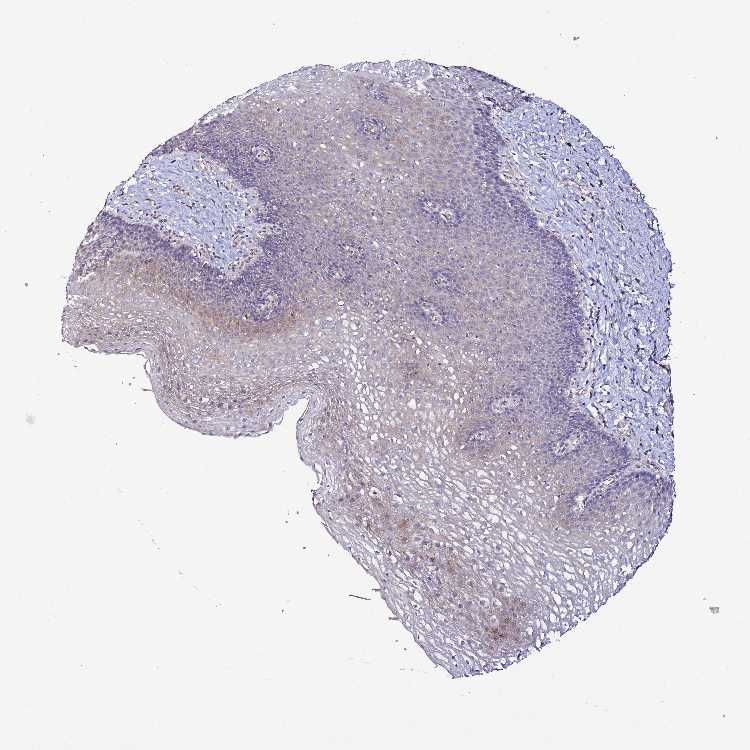

ESOPHAGUS - Antibody stainingi

Antibody staining in the annotated cell types in the current human tissue is reported as not detected, low, medium, or high, based on conventional immunohistochemistry profiling in selected tissues. This score is based on the combination of the staining intensity and fraction of stained cells.

Each image is clickable and will lead to virtual microscopy that enables deeper exploration of all samples and also displays staining intensity scores, fraction scores and subcellular localization as well as patient and tissue information for each sample.

Antibody HPA046184

Squamous epithelial cells Low